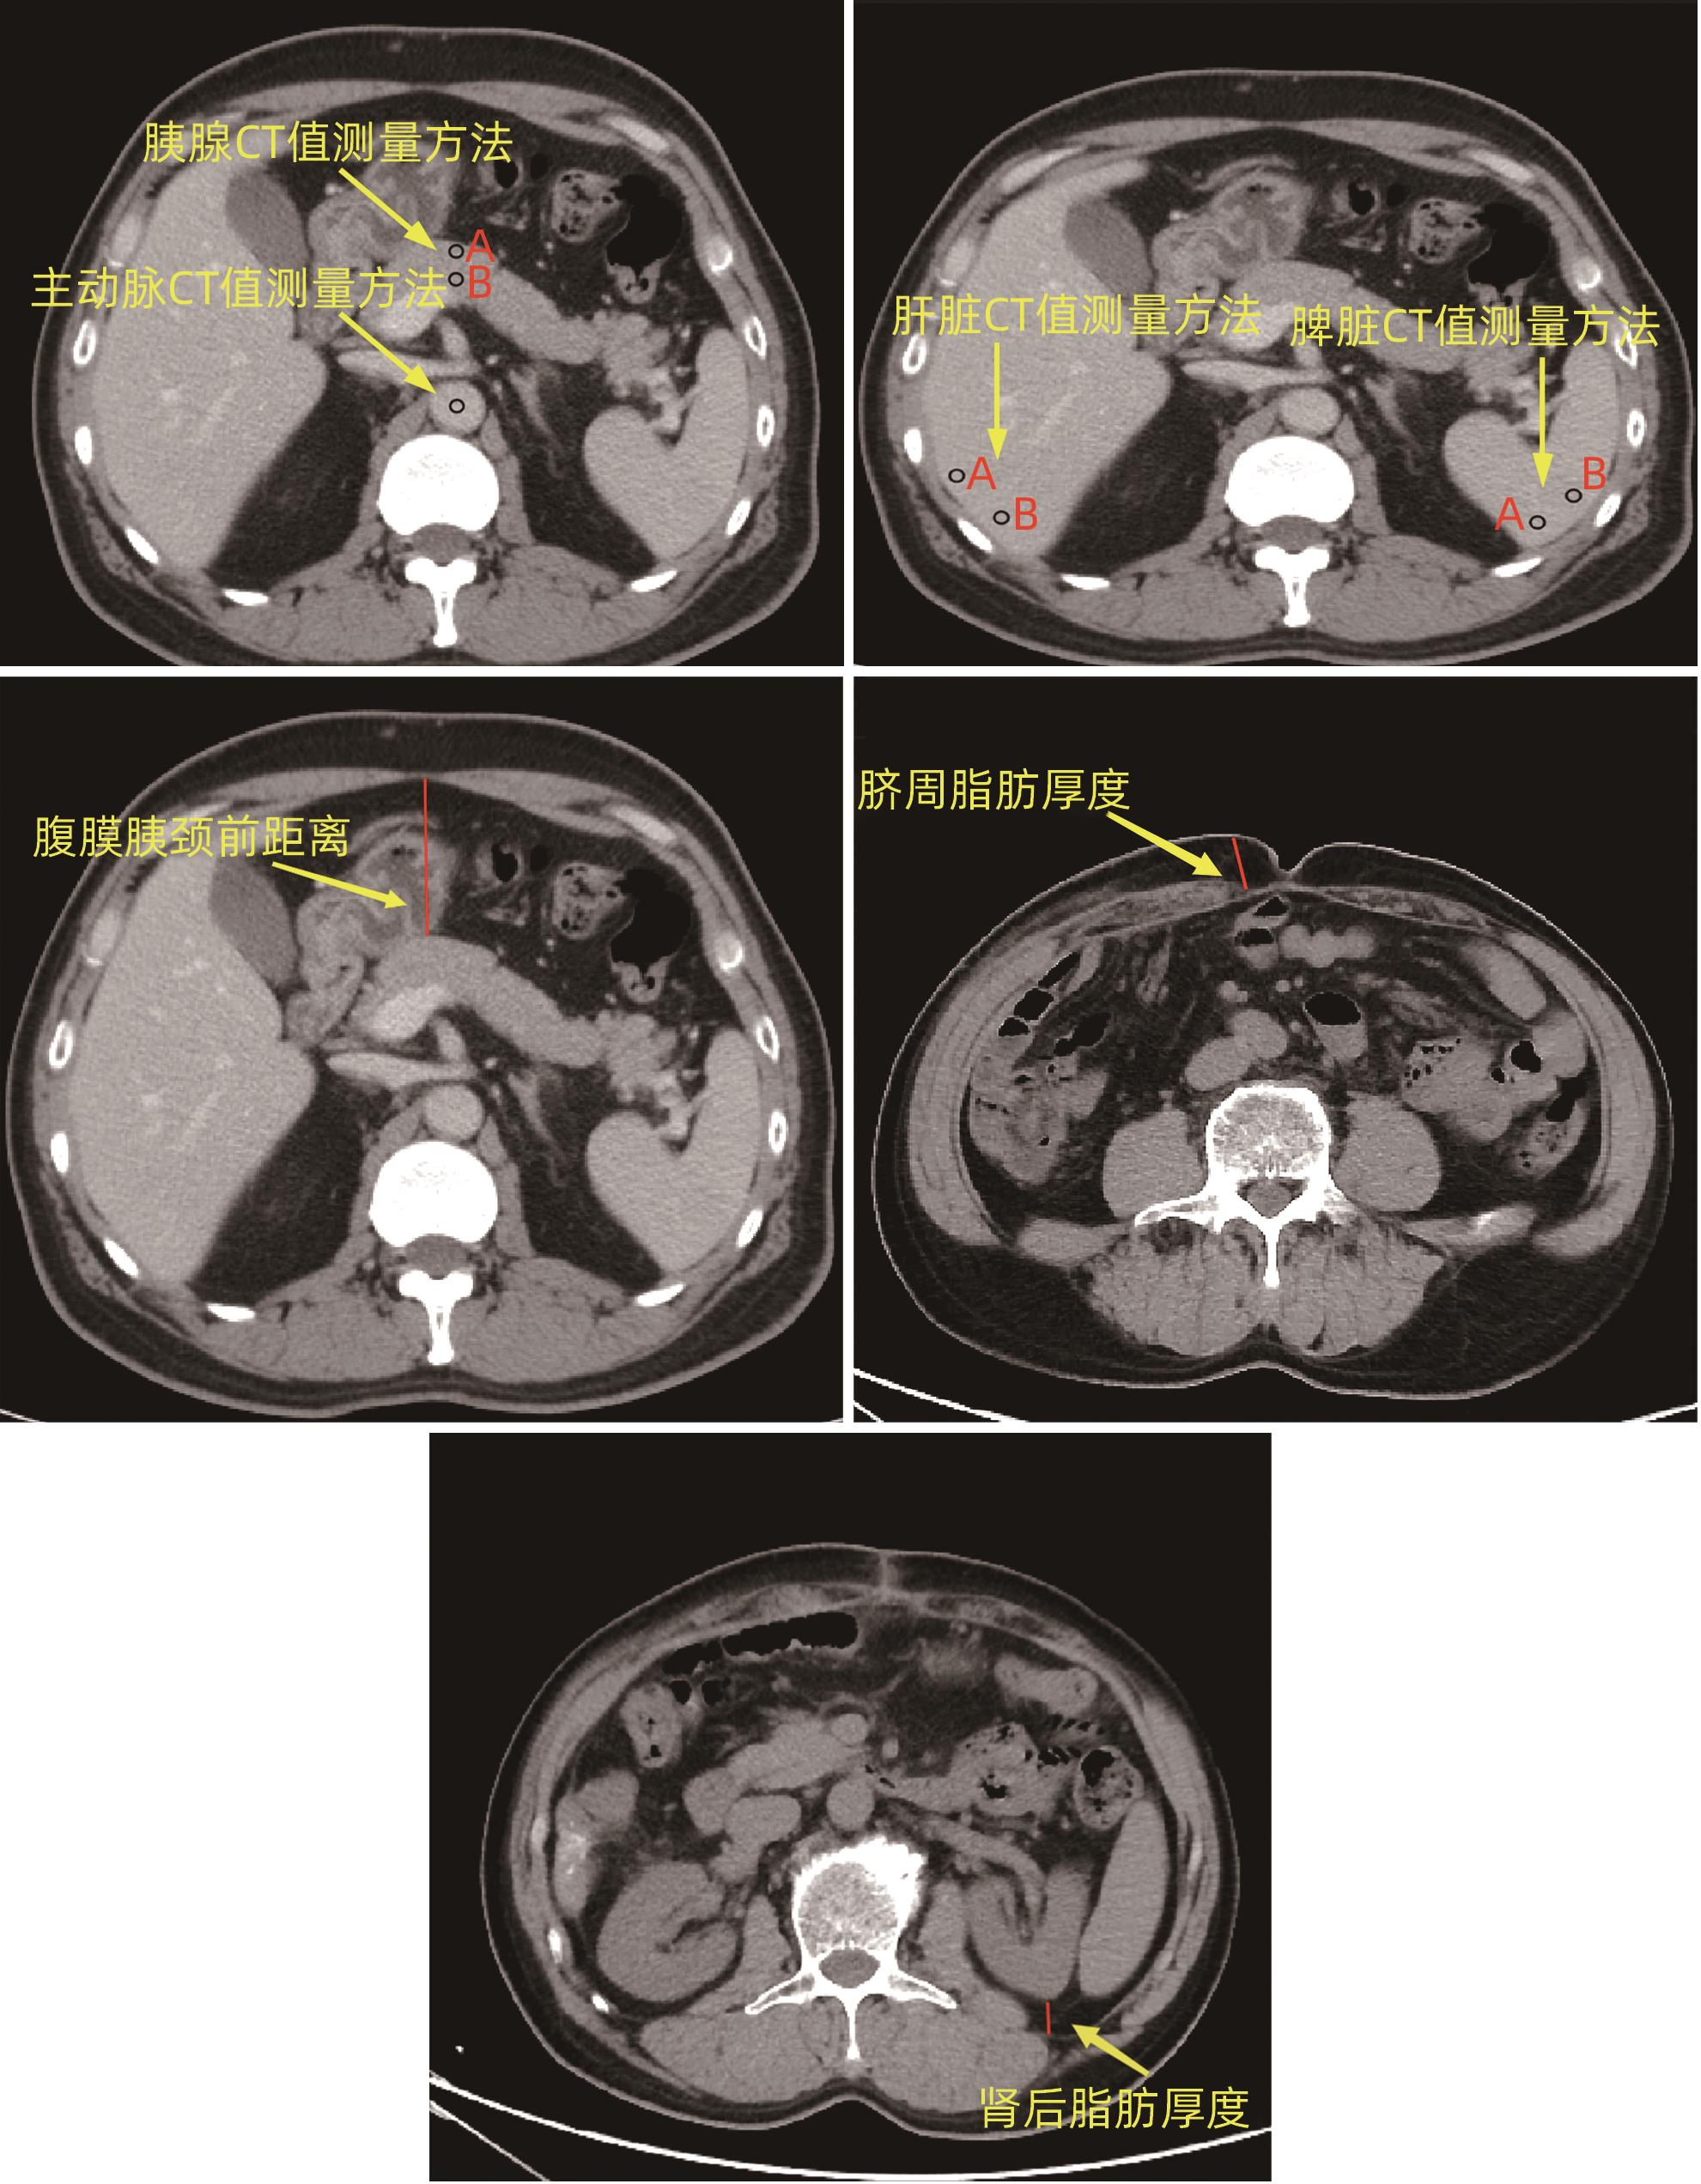

Value of preoperative alanine aminotransferase/aspartate aminotransferase combined with multi-phase CT radiological indicators in predicting clinically relevant pancreatic fistula after pancreaticoduodenectomy

Junhao PAN, Jian XIN, Chunhui WANG

2024, 40(9): 1859-1867. DOI: 10.12449/JCH240922

Abstract(849) HTML (361) PDF (2208KB)(50)

Abstract:

Objective  To investigate the risk factors for clinically relevant postoperative pancreatic fistula (CR-POPF) after pancreaticoduodenectomy (PD), and to establish a predictive model for early identification of CR-POPF.  Methods  A total of 244 patients who underwent PD in General Hospital of Northern Theater Command from January 2019 to October 2023 were collected, and based on strict inclusion and exclusion criteria, 179 patients were finally enrolled in this study. According to the presence or absence of CR-POPF, these patients were divided into non-CR-POPF group with 120 patients and CR-POPF group with 59 patients. Univariate and multivariate logistic regression analyses were used to determine the independent risk factors for CR-POPF, and a nomogram model was established based on such factors. The receiver operating characteristic (ROC) curve was used to assess the predictive performance of the model, the calibration curve was used to evaluate the calibration degree of the model, and the clinical decision curve and the clinical impact curve were used to analyze and validate the clinical application value of the model. The chi-square test or the Fisher’s exact test was used for comparison of categorical data between groups; the independent-samples t test was used for comparison of normally distributed continuous data between two groups, and the Mann-Whitney U test was used for comparison of continuous data with skewed distribution between two groups.  Results  Among the 179 patients, 59 (33.0%) developed CR-POPF. The multivariate Logistic regression analysis showed that alanine aminotransferase/aspartate aminotransferase (odds ratio [OR]=2.221, P=0.004), main pancreatic duct diameter (OR=0.276, P=0.022), the distance between the peritoneum and the anterior pancreatic neck (OR=1.034, P=0.027), and extracellular volume fraction (OR=0.001, P=0.005) were independent risk factors for CR-POPF. Based on the above four independent risk factors, a nomogram was established to predict CR-POPF after PD, with an area under the ROC curve of 0.837, a sensitivity of 0.932, and a specificity of 0.725. The decision curve and the clinical impact curve also showed that the nomogram had good clinical practicability.  Conclusion  Preoperative clinical indicators combined with multi-phase CT have a good performance in predicting CR-POPF after PD, which can be used to early identify patients at high risk of pancreatic fistula before surgery and provide further guidance for clinical work.